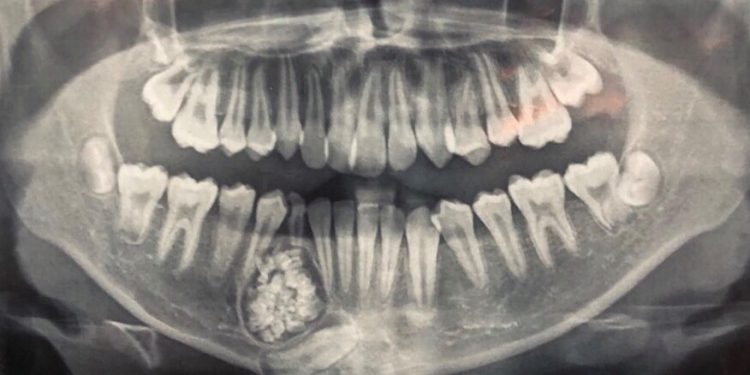

Bệnh viện Đa khoa tỉnh Khánh Hòa cho biết vừa thực hiện ca phẫu thuật hi hữu lấy gần 100 cái răng của một bệnh nhân. Ngày 15/6/2019, bác sĩ Nguyễn Đức Tuấn – Trưởng Khoa Răng hàm mặt, Bệnh viện (BV) đa khoa tỉnh Khánh Hòa, cho biết các bác sĩ của BV tỉnh này phối hợp với Bệnh viện Răng hàm mặt Trung ương TP. Hồ Chí Minh phẫu thuật thành công lấy ra gần 100 cái răng trong khối u ở hàm dưới bệnh nhân Hoàng Gia K. (13 tuổi, ngụ TP Nha Trang). Những chiếc răng nhỏ có đầy đủ thân răng, tủy răng và chân răng. Bệnh nhân K. được người nhà đưa đến BV đa khoa tỉnh Khánh Hòa khám và thực hiện chỉnh hình răng mọc lệch và chậm thay răng mới. Qua chụp X-quang, các bác sĩ của BV Khánh Hòa bất ngờ phát hiện có 1 khối u răng ở xương hàm dưới.

U răng được phân thành 2 loại: Compound odontoma và Complex Odontoma. Thuờng phân biệt rõ trên phim X-quang:

- Compound odontoma (U răng kết hợp) biểu hiện dưới dạng các khối cản quang có dạng các mẫu răng nhỏ, một hốc u răng có thể chứa từ vài chục đến vài trăm chiếc răng nhỏ li ti có kích thuớc từ chưa tới một mm đến vài mm, các chiếc răng tí hon này, phân biệt rõ đâu là men răng, ngà răng, tuỷ răng.

- Complex Odontoma (U răng hỗn hợp) biểu hiện là một khối cản quang có đậm độ khác nhau, không phân biệt được đâu là men răng, ngà răng.